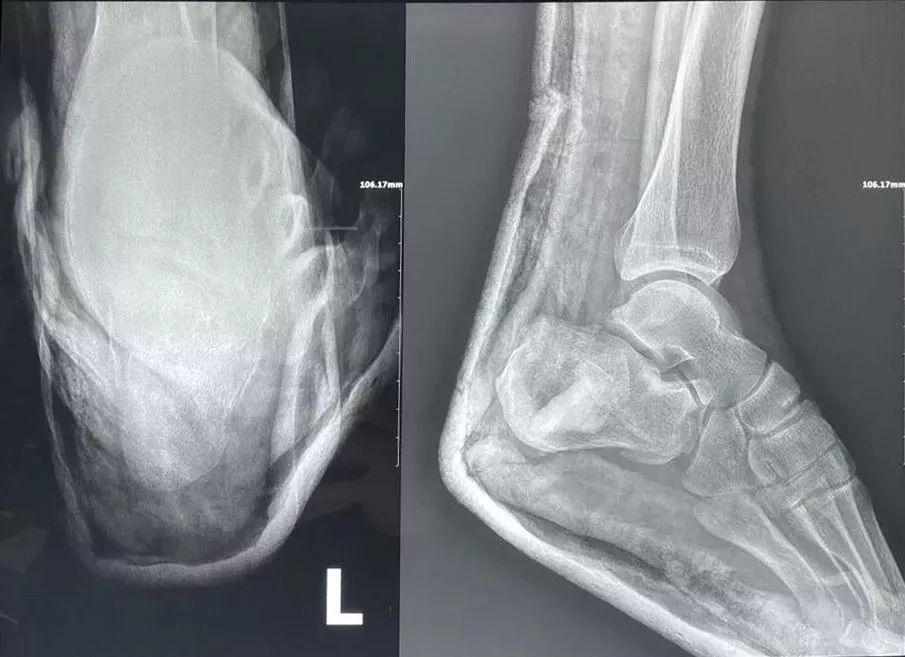

手術(shù)中透視跟骨骨折解剖復(fù)位